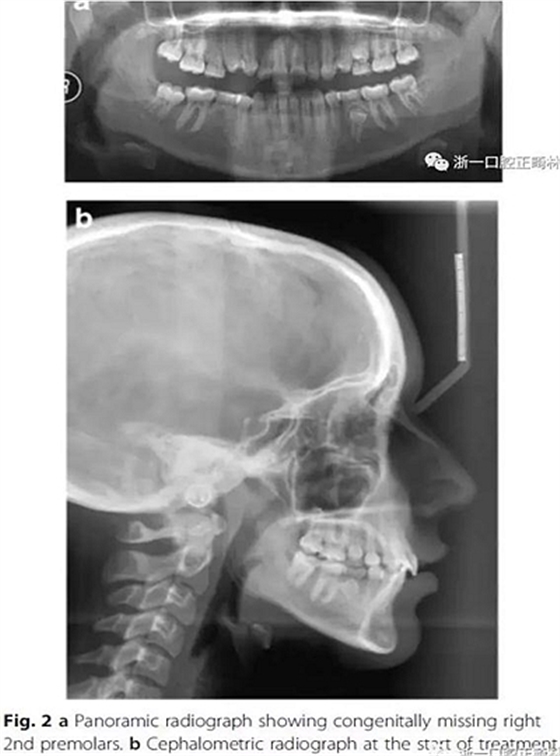

影像學檢查,右側第二前磨牙和所有第三磨牙先天性缺失;

頭側分析,骨性I類關系,高角型